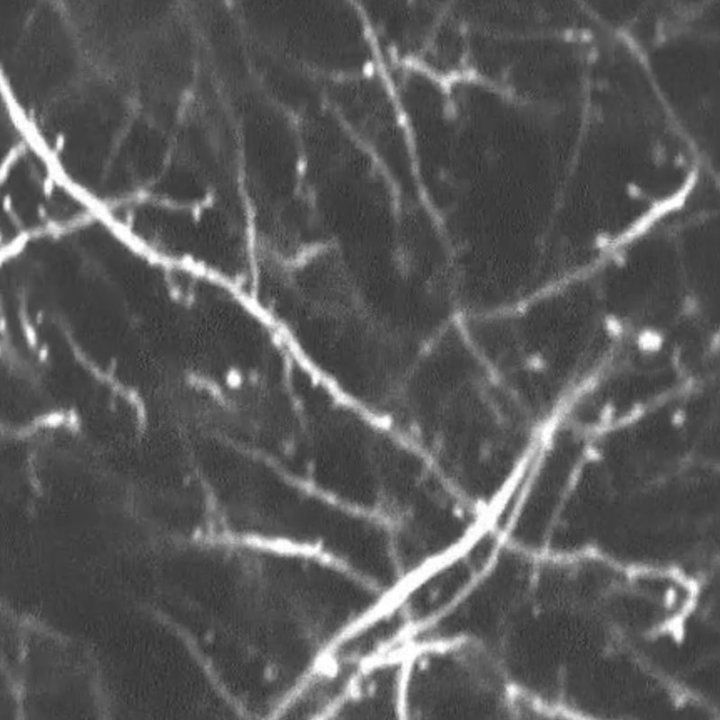

An image of dendrites showing the dendritic spines (small bumps) essential to communication between neurons. Researchers found that, after a concussion, neurons form an excessive number of these spines, leading to “noisy” signals in the brain that can affect cognition. Credit: Elma Frias/Stryker Lab

Using advanced imaging techniques, Frias observed the effects of TBI on dendritic spines, the primary site of excitatory communication between neurons, over the course of multiple days.

In healthy conditions, neurons show a fairly consistent rate of spine formation, maturation and elimination – dynamics that support learning and memory. But after a single mild concussion, mouse cortical neurons showed a massive burst of newly formed spines and continued to make excessive spines for as long as they were measured.

“Some may find this counterintuitive at first, assuming more dendritic spines would be a good thing for making new memories,” said co-senior author Susanna Rosi, PhD, a professor of physical therapy and neurological surgery at UCSF at the time of the study, now also at Altos Labs. “But in actuality, having all too many new spines is like being in a noisy room – when too many people are talking, you can’t hear the information you need.”

These new spines didn’t stick around for very long, however, and most were removed within days, meaning they hadn’t formed lasting functional synaptic connections.